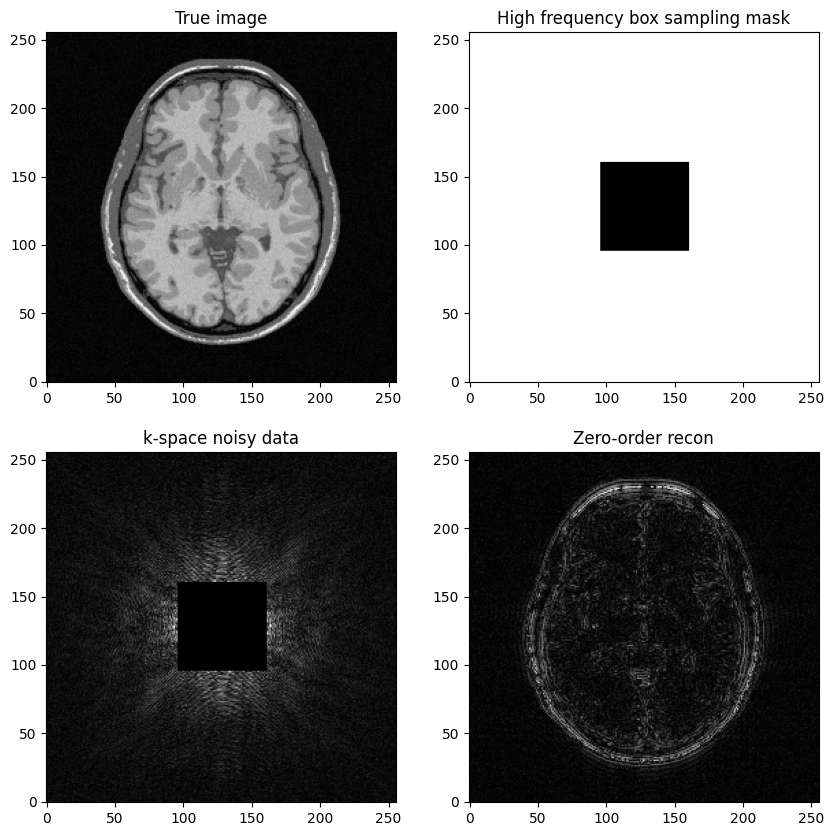

a high-frequency Cartesian mask is defined as the complementary set of the box defined in 2)

Question: Based on the previous example, try to construct a k-space mask that consists of the removing the central box centered in .

Then, replicate the same steps:

Generate noisy masked data

Perform zero-filled MR image recon

Visualize results and study the impact of both the noise level and the mask size

fig, axs = plt.subplots(2, 2, figsize=(10, 10) )

axs[0,0].imshow(mri_img, cmap='Greys_r')

axs[0,0].set_title("True image")

axs[0,1].imshow(kspace_maskbox, cmap='Greys_r')

axs[0,1].set_title("High frequency box sampling mask")

axs[1,0].imshow(np.abs(kspace_data), cmap='gray', vmax=1*np.abs(kspace_data).max())

axs[1,0].set_title("k-space noisy data")

axs[1,1].imshow(np.abs(image_rec0), cmap='Greys_r')

axs[1,1].set_title("Zero-order recon")

plt.show()